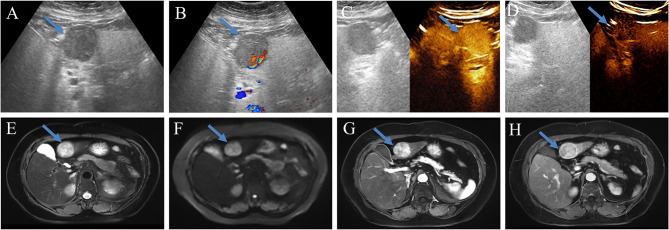

Purpose: To develop and validate a reliable preoperative non-invasive diagnostic model for dual-phenotype hepatocellular carcinoma (DPHCC) by integrating multimodal imaging and clinical indicators, thereby facilitating clinical decision-making.

Patients and methods: 222 pathologically confirmed patients (61 with DPHCC, 161 with non-DPHCC) were retrospectively enrolled in this study and randomly assigned to training and validation cohorts in an 8:2 ratio. Serological and multimodal imaging characteristics were analyzed. Univariate and multivariate logistic regression analyses identified independent DPHCC predictors and built a nomogram. Model performance and clinical utility were assessed by receiver operating characteristic (ROC) and decision curve analysis (DCA) curve respectively. The calibration curve was used to verify the model. Recurrence-free survival (RFS) was assessed using Kaplan-Meier and Log rank tests.

Results: In multivariate analysis, age (OR=0.91; P < 0.001), LDH (OR=1.03; P=0.002), PT (OR=0.14; P < 0.001), AFP (OR=4.04; P=0.019), Adler grade (OR=0.17; P=0.037), non-enhancing area (OR=8.30; P=0.004), arterial phase hyperenhancement (OR=0.12; P=0.015) and enhancing capsule (OR=0.32; P=0.04) were independent predictors of DPHCC. The nomogram achieved a robust predictive performance with C-index (0.92 vs 0.87) and accuracy (0.87 vs 0.86) in the training and validation cohorts. In addition, the calibration curve and DCA also showed good model performance. DPHCC patients had significantly lower RFS than non-DPHCC patients (P = 0.037).

Conclusion: A nomogram was established for non-invasive prediction of DPHCC risk utilizing multimodal imaging combined with clinical indicators to help achieve personalized treatment.